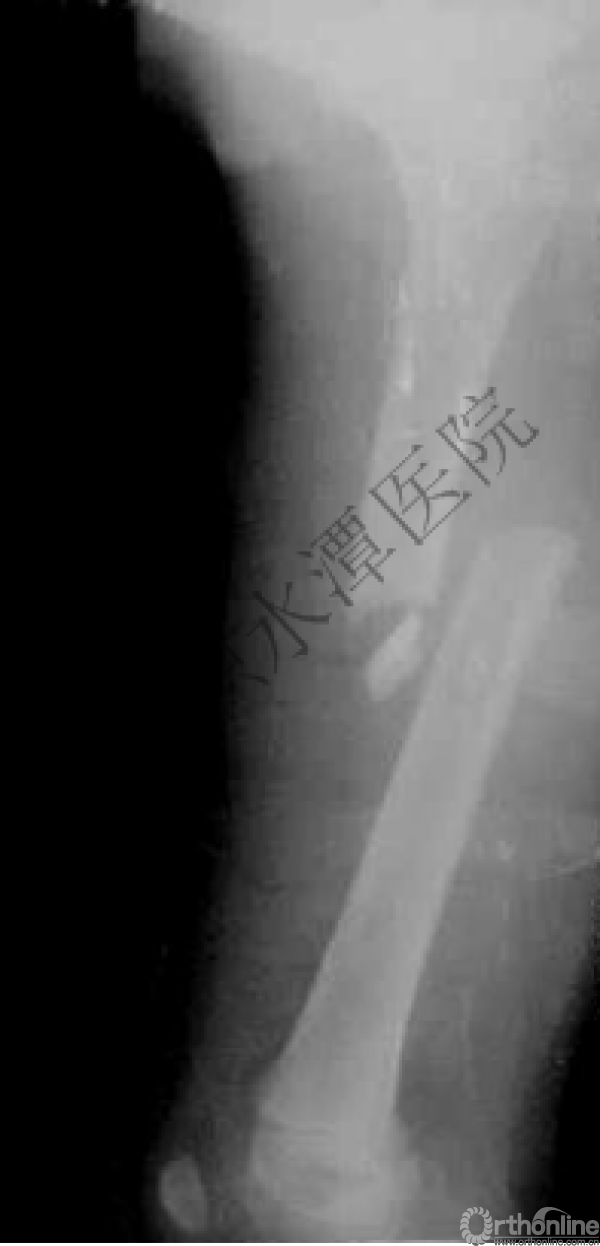

闭合复位再固定加尾帽

又过了4年!时间来到2015年

一年以后顺利愈合,实则危机四伏

数月后再骨折!牵引!

髋人字支具

外固定架术后一年

整整11年!是否治疗终结?